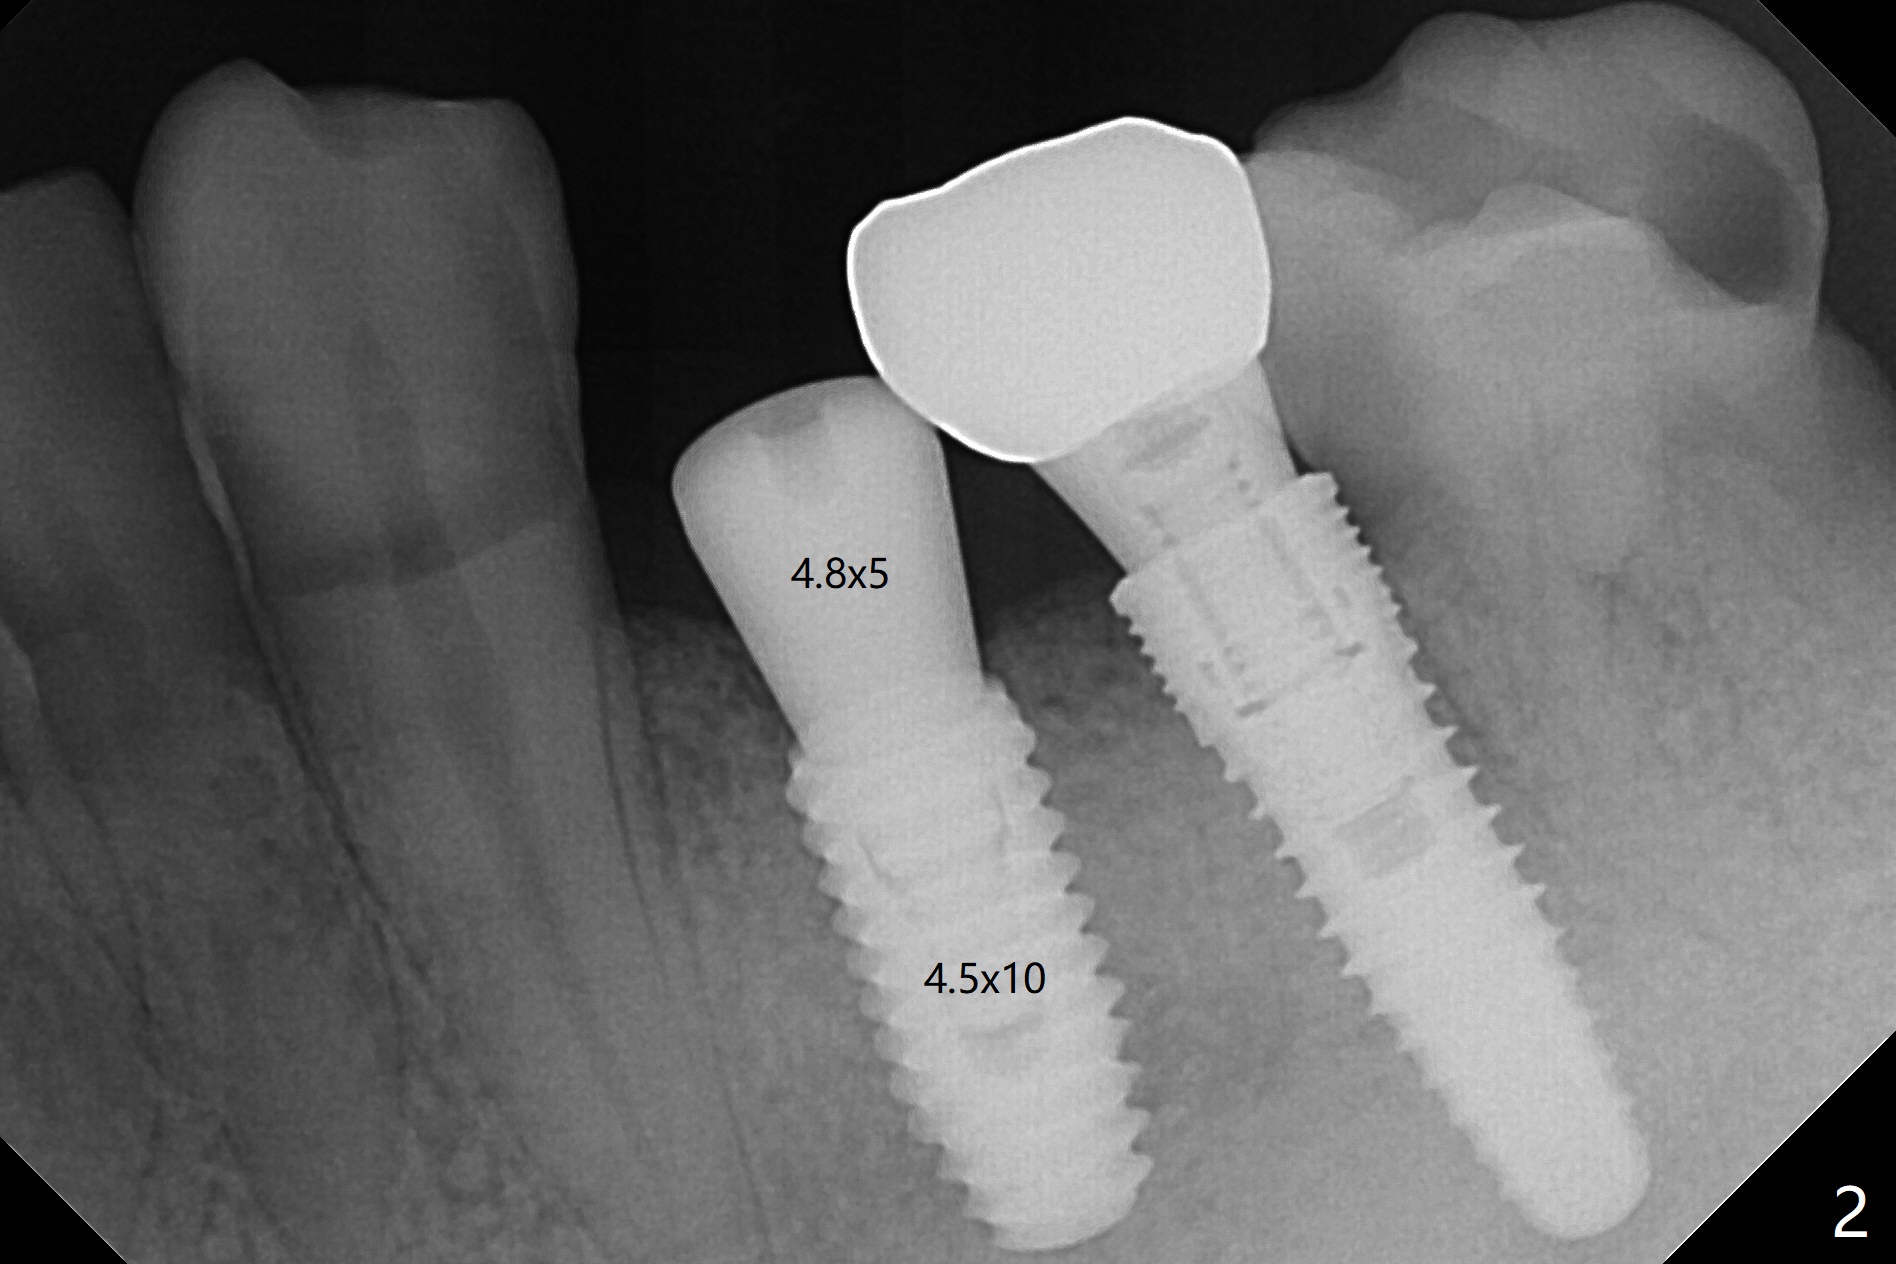

To remove the subgingival residual root of the tooth #12, buccal flap is raised, which provides access to see thread formation in the coronal portion of the socket following use of cortical tap. Bone harvested from osteotomy is placed in the remaining buccal socket (Fig.1). Bone density is so high at #21 that 4.5x8.5 and 4.5x10 mm drills are used before placement of a 4.5x10 mm with 12 mm offset in addition to use of cortical tap and back up of the implant several times (Fig.2).